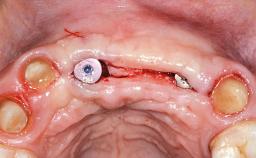

Replacement of Four Incisors with a Fixed Partial Denture on Two Narrow-Neck Implants after Implant Failure

| Case Type | Extended Space |

|---|---|

| Jaw | Maxilla |

| Area | Anterior |

| # of Teeth | 4 |

| # of Implants | 2 |

| Type of Implants | One-Piece|Reduced-Diameter |